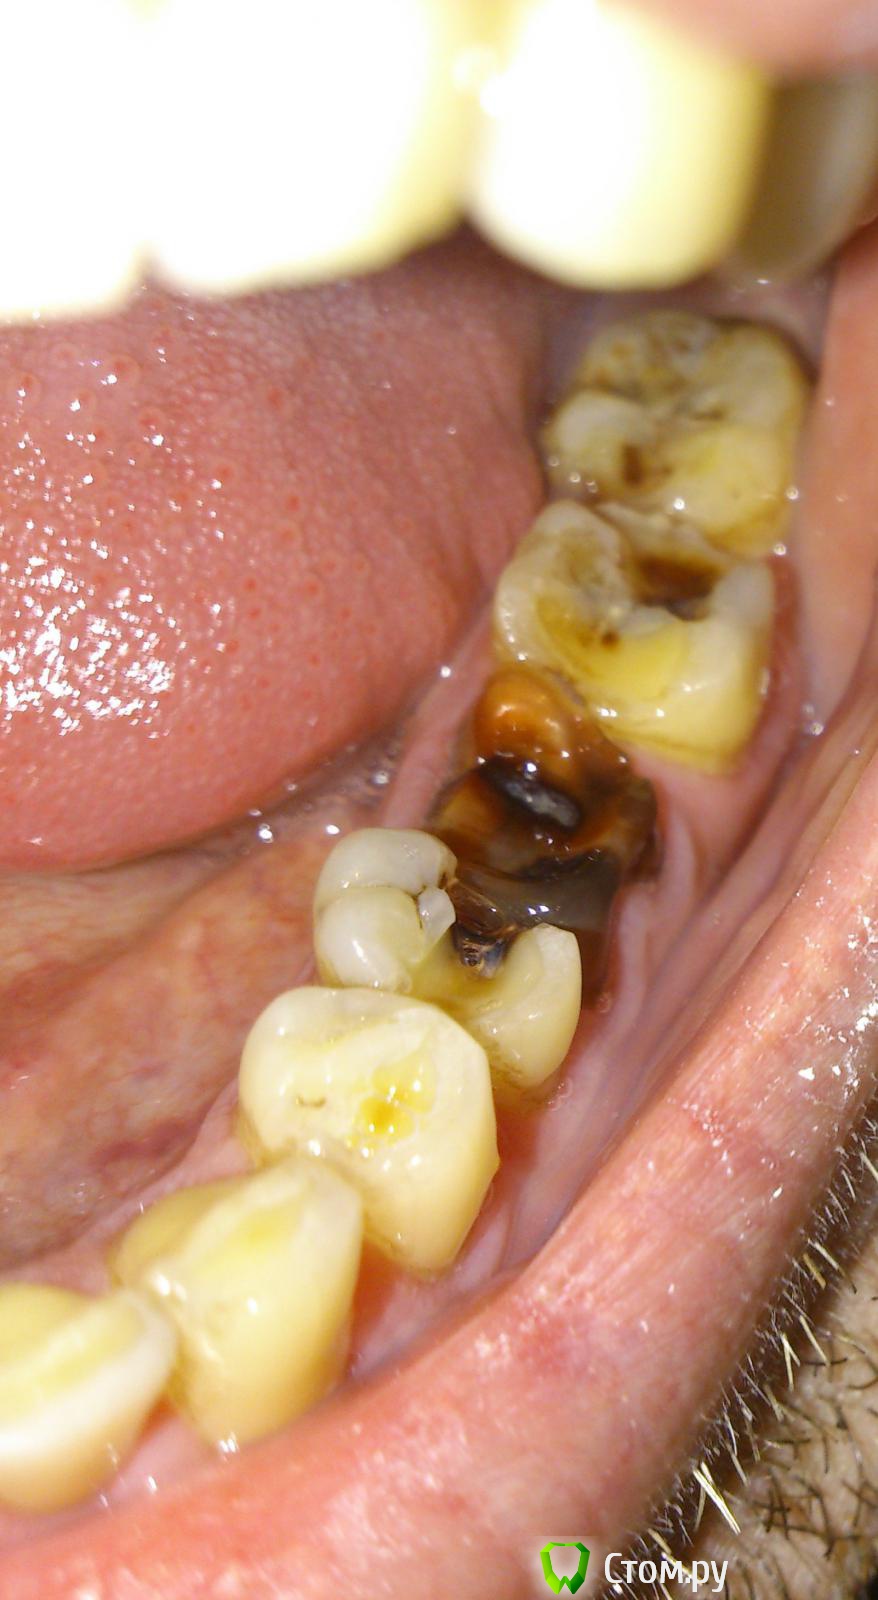

govorov Опубликовано 5 декабря, 2013 Поделиться Опубликовано 5 декабря, 2013 Подскажите, пожалуйста,что и в какой последовательности лучше делать с этими зубами?Зубы на фото в ссылке ниже. 6-й давно лечили, пломбировали. Несколько лет назад откололась примерно половина зуба с пломбой. Хотели вырвать, но не настаивали, я оставил. Через некоторое время потемнел, но особо не беспокоил. Сейчас, иногда, вечером или ночью болит. Днём нормально: не болит и есть на нём нормально. Соседние, вроде надо лечить? Нужно ли сначала удалять или что-то делать с этим 6-м? Если нужно удалять 6-й, можно ли сразу, вместо вырванного, вставить имплант, или вырвать, потом лечить остальные, потом делать имплант? Снимок корня 6-го _20131129_15633 - сделан 2013-11-29, _20121013_9451 - примерно год назад.Где это лучше делать (Долгопрудный, Москва)? И сколько это может стоить?Спасибо! Ссылка на комментарий

IvanK Опубликовано 6 декабря, 2013 Поделиться Опубликовано 6 декабря, 2013 Спасибо большое за ответы! Скажите ещё пожалуйста, какой главный аргумент за удаление 6-го? Не может ли быть так, что болят соседние, и достаточно их вылечить, а этот — 6-й — чёрный или красный, половина, но не болит ни кому не мешает?соседние тоже могут болеть... причем большая их часть на фото... Ссылка на комментарий

IvanK Опубликовано 6 декабря, 2013 Поделиться Опубликовано 6 декабря, 2013 Зуб нужен для жевания. Ваш зуб не выполняет свою функцию. Мало того, что он разрушен, он еще является источником хронической инфекцией (разрушенные корни, "киста")не хотите - не удаляйте, никто Вас не заставляет... с такой политикой боюсь предположить что мы увидим на панорамном снимке... Ссылка на комментарий

DmitrySH Опубликовано 6 декабря, 2013 Поделиться Опубликовано 6 декабря, 2013 (изменено) Вокруг корней 6-го зуба достаточно большие очаги воспаления. Зачем хранить в себе очаг инфекции? IvanK, опередил Изменено 6 декабря, 2013 пользователем dmitrySH 1 Ссылка на комментарий